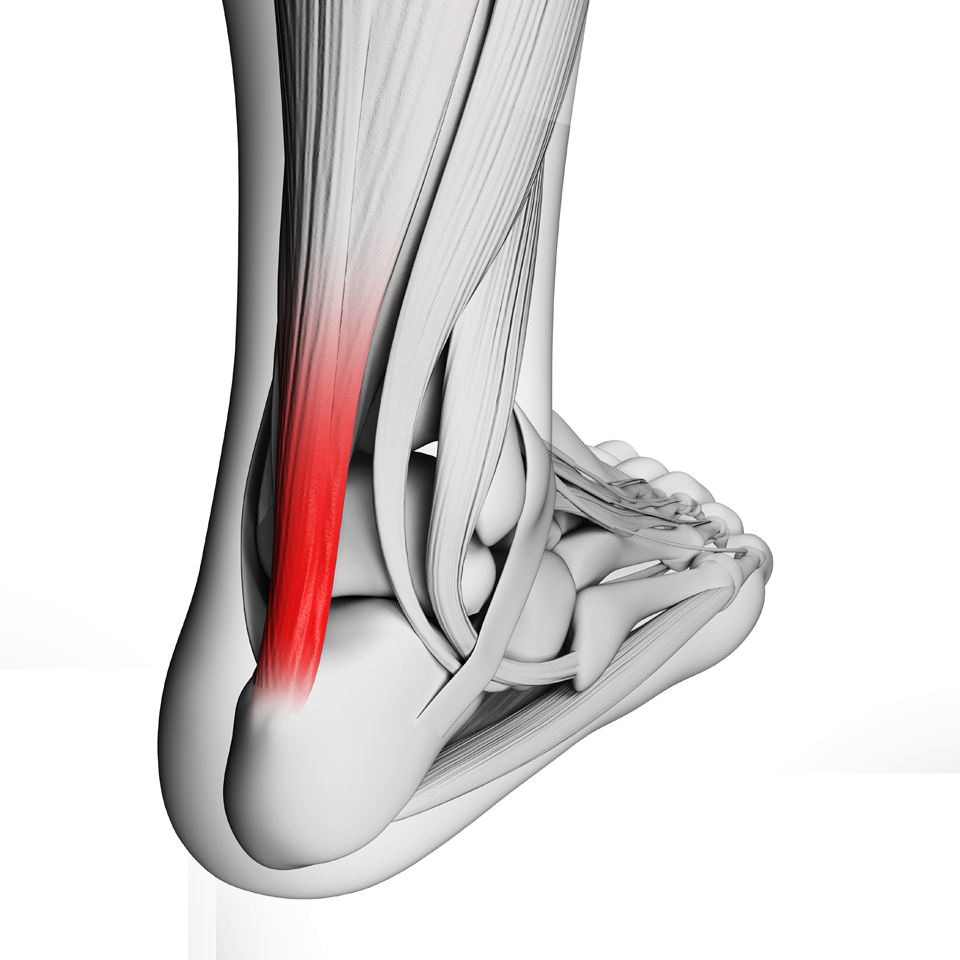

A tendinite de Aquiles é aquela dor chata que aparece na parte de trás do seu calcanhar, bem ali onde o músculo da panturrilha se liga ao osso do pé. Sabe, é uma inflamação desse tendão forte que usamos para correr, pular e até para andar. Quando exigimos demais dele, ou quando ele já está cansado e fraco, o problema aparece.

As palmilhas e órteses são como um abraço para o seu pé, sabe? Elas ajudam a realinhar a pisada e a distribuir o peso de forma mais uniforme. Isso diminui a sobrecarga no tendão de Aquiles, que é o que causa a dor. É um jeito prático de dar um alívio direto na causa do problema.

Existem vários tipos, desde as mais simples que você compra pronta até as feitas sob medida por um profissional. Para a tendinite de Aquiles, o foco é no suporte do arco do pé e no amortecimento do calcanhar. Isso evita que o tendão seja esticado demais a cada passo. O importante é sentir que o seu pé está mais estável.